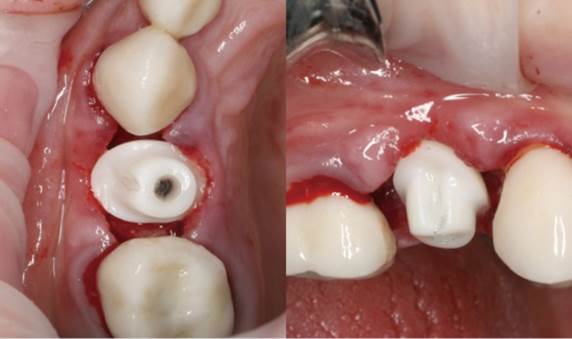

Clinical case: Extraction, immediate implant placement, & provisionalization

- Courtesy of Dr. Iulian Filipov, Romania -

Keywords

AnyRidge, R2GATE, guided surgery, immediate placement, immediate provisionalization, initial stability, Dr. Iulian Filipov, #25, maxillary posterior, immediate loading, Mega ISQ

Products:

AnyRidge implant system, R2GATE, MEGA ISQ, Digital prosthesis